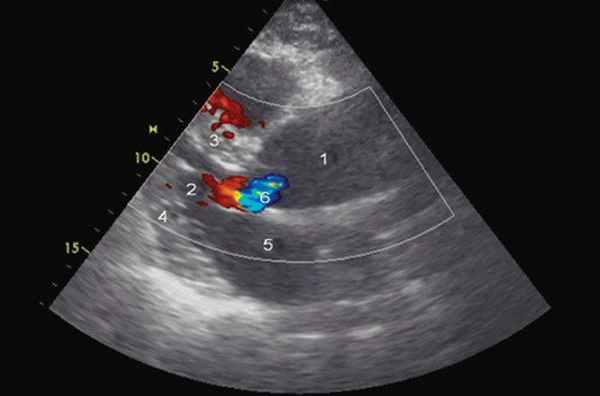

Рис. 1. Эхокардиограмма больного Ж. Режим ЦДК. Парастернальная позиция по длинной оси.

1 - аорта, 2 - левый желудочек, 3 - межжелудочковая перегородка, 4 - задняя стенка левого желудочка, 5 - левое предсердие, 6 - регургитация на аортальном клапане.

Помимо гипертрофии миокарда левого желудочка, склеротически измененных створок аортального клапана и наличия его недостаточности I степени, обращало на себя внимание расширение восходящего отдела аорты до 4,5-5,1 см (на различных уровнях) (рис. 1). Исследование средних отделов восходящей аорты (рис. 2) позволяло выявить нитевидную, невыраженно флотирующую структуру, расположенную по передней стенке аорты, формирующую истинный и ложный каналы аорты, которые более детально верифицировались в режиме ЦДК (рис. 3). В слепом участке ложного канала определялись тромботические массы. При исследовании из супрастернального доступа в области дистального отдела восходящей аорты и ее дуги лоцировался участок отслоения интимы (рис. 4). В остальных отделах аорты, доступных для визуализации, патологии выявлено не было. Таким образом, ультразвуковое исследование сердца позволило диагностировать расслаивающую аневризму восходящего отдела и дуги аорты (тип II по De Bakey). Проведенная МСКТ подтвердила данный диагноз (рис. 5).